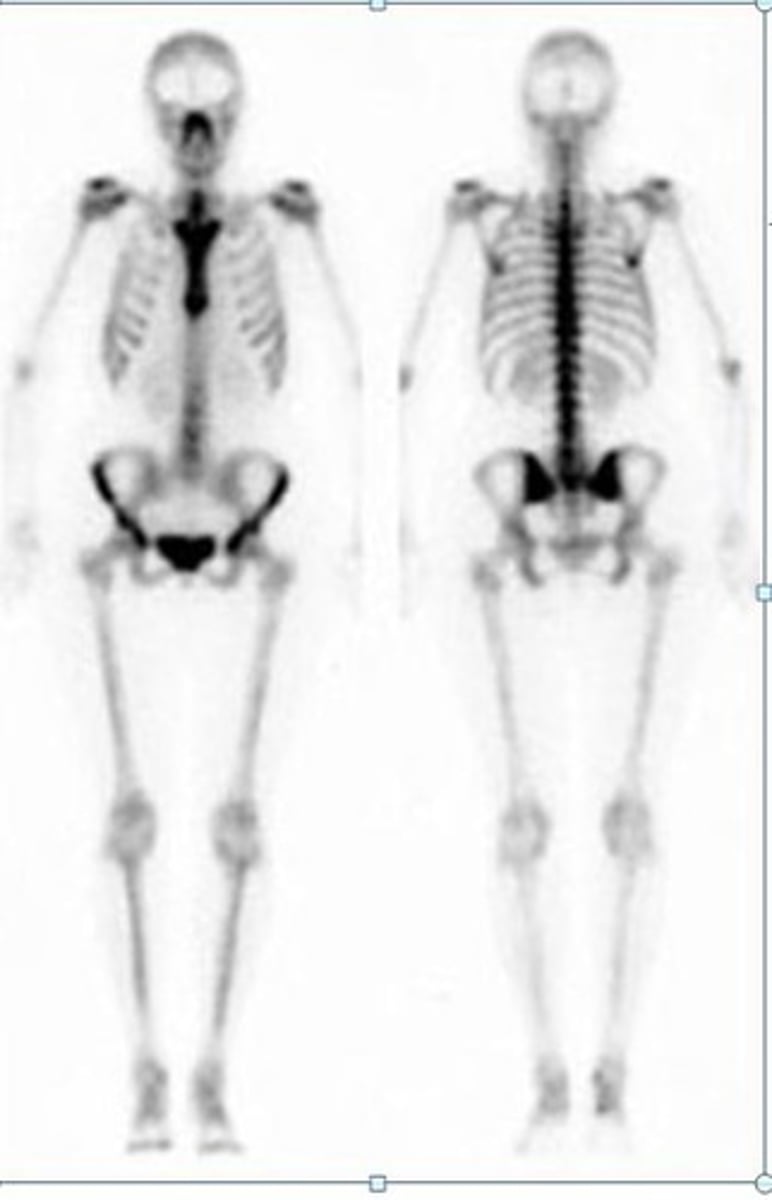

Bone scan

Looks at the skeletal system

-Radioactive phosphate coupled to technetium-99 (taken up by osteoblast & incorporated into bone --> scanned 3 hours later)

When should you order a bone scan?

Bone metastasis, osteomyelitis, trauma/fractures, metabolic bone diseases, avascular necrosis, arthritic disease